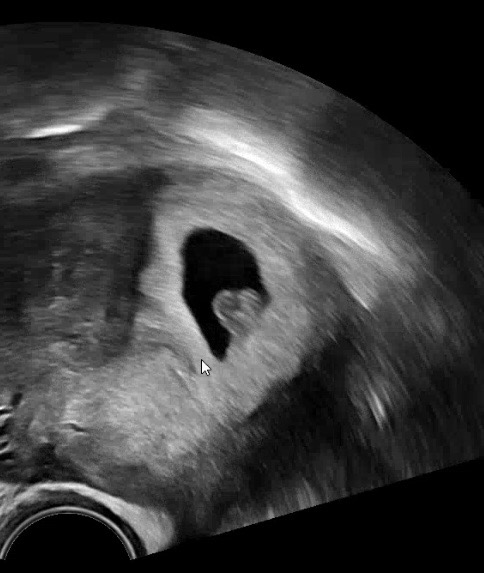

오늘 아가 초음파 보고 심장소리도 듣고 왔어요! 지난주에는 아기집 가운데에 있더니 오늘은 어째 아기집 벽에 착 달라붙어있어서 🩷로 보여요!! 아직 팔다리가 없다던데 아기가 돌아다니나요?🙊 난임병원 담당 원장님이 아기가 주수에 맞게 잘 크고 있고 다 좋다고 하시면서 다음주부터는 2번방 선생님께 진료보면되고 우리는 둘째 만들때 다시 만나자고 하시더라고요! 완전한 졸업까지는 아직 7주나 더 남았지만 1차 졸업한 것 같아서 너무 행복해요! 모두 행복한 금요일 보내시길 바래요✨

초음파 사진이 이렇게 귀여울수도 있군요🥹